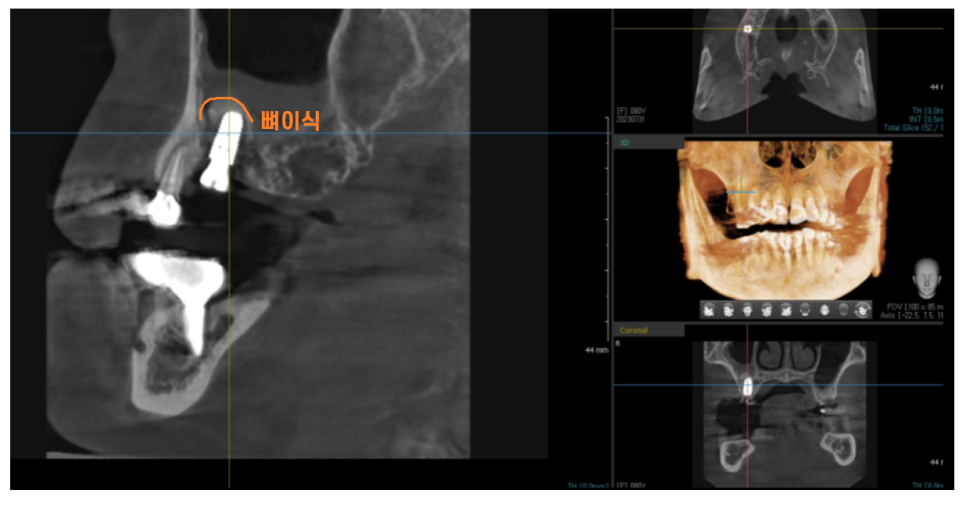

3년동안의 골다공증 치료

뼈가 약하신 환자분이셔서

뼈이식까지 진행 후 수술을 했는데요.

돔 형태로 예쁘게 상악동이 올라갔네요~

수술이 아주 잘되었습니다.